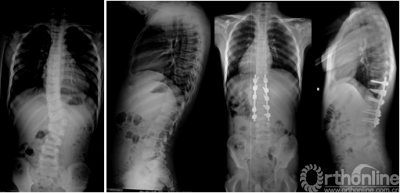

13岁女性患儿,特发性脊柱侧凸(双胸弯,Lenke分型2A-)。术前侧凸角度达80°,行单一后路手术,选择性融合,最大限度保留腰椎活动度